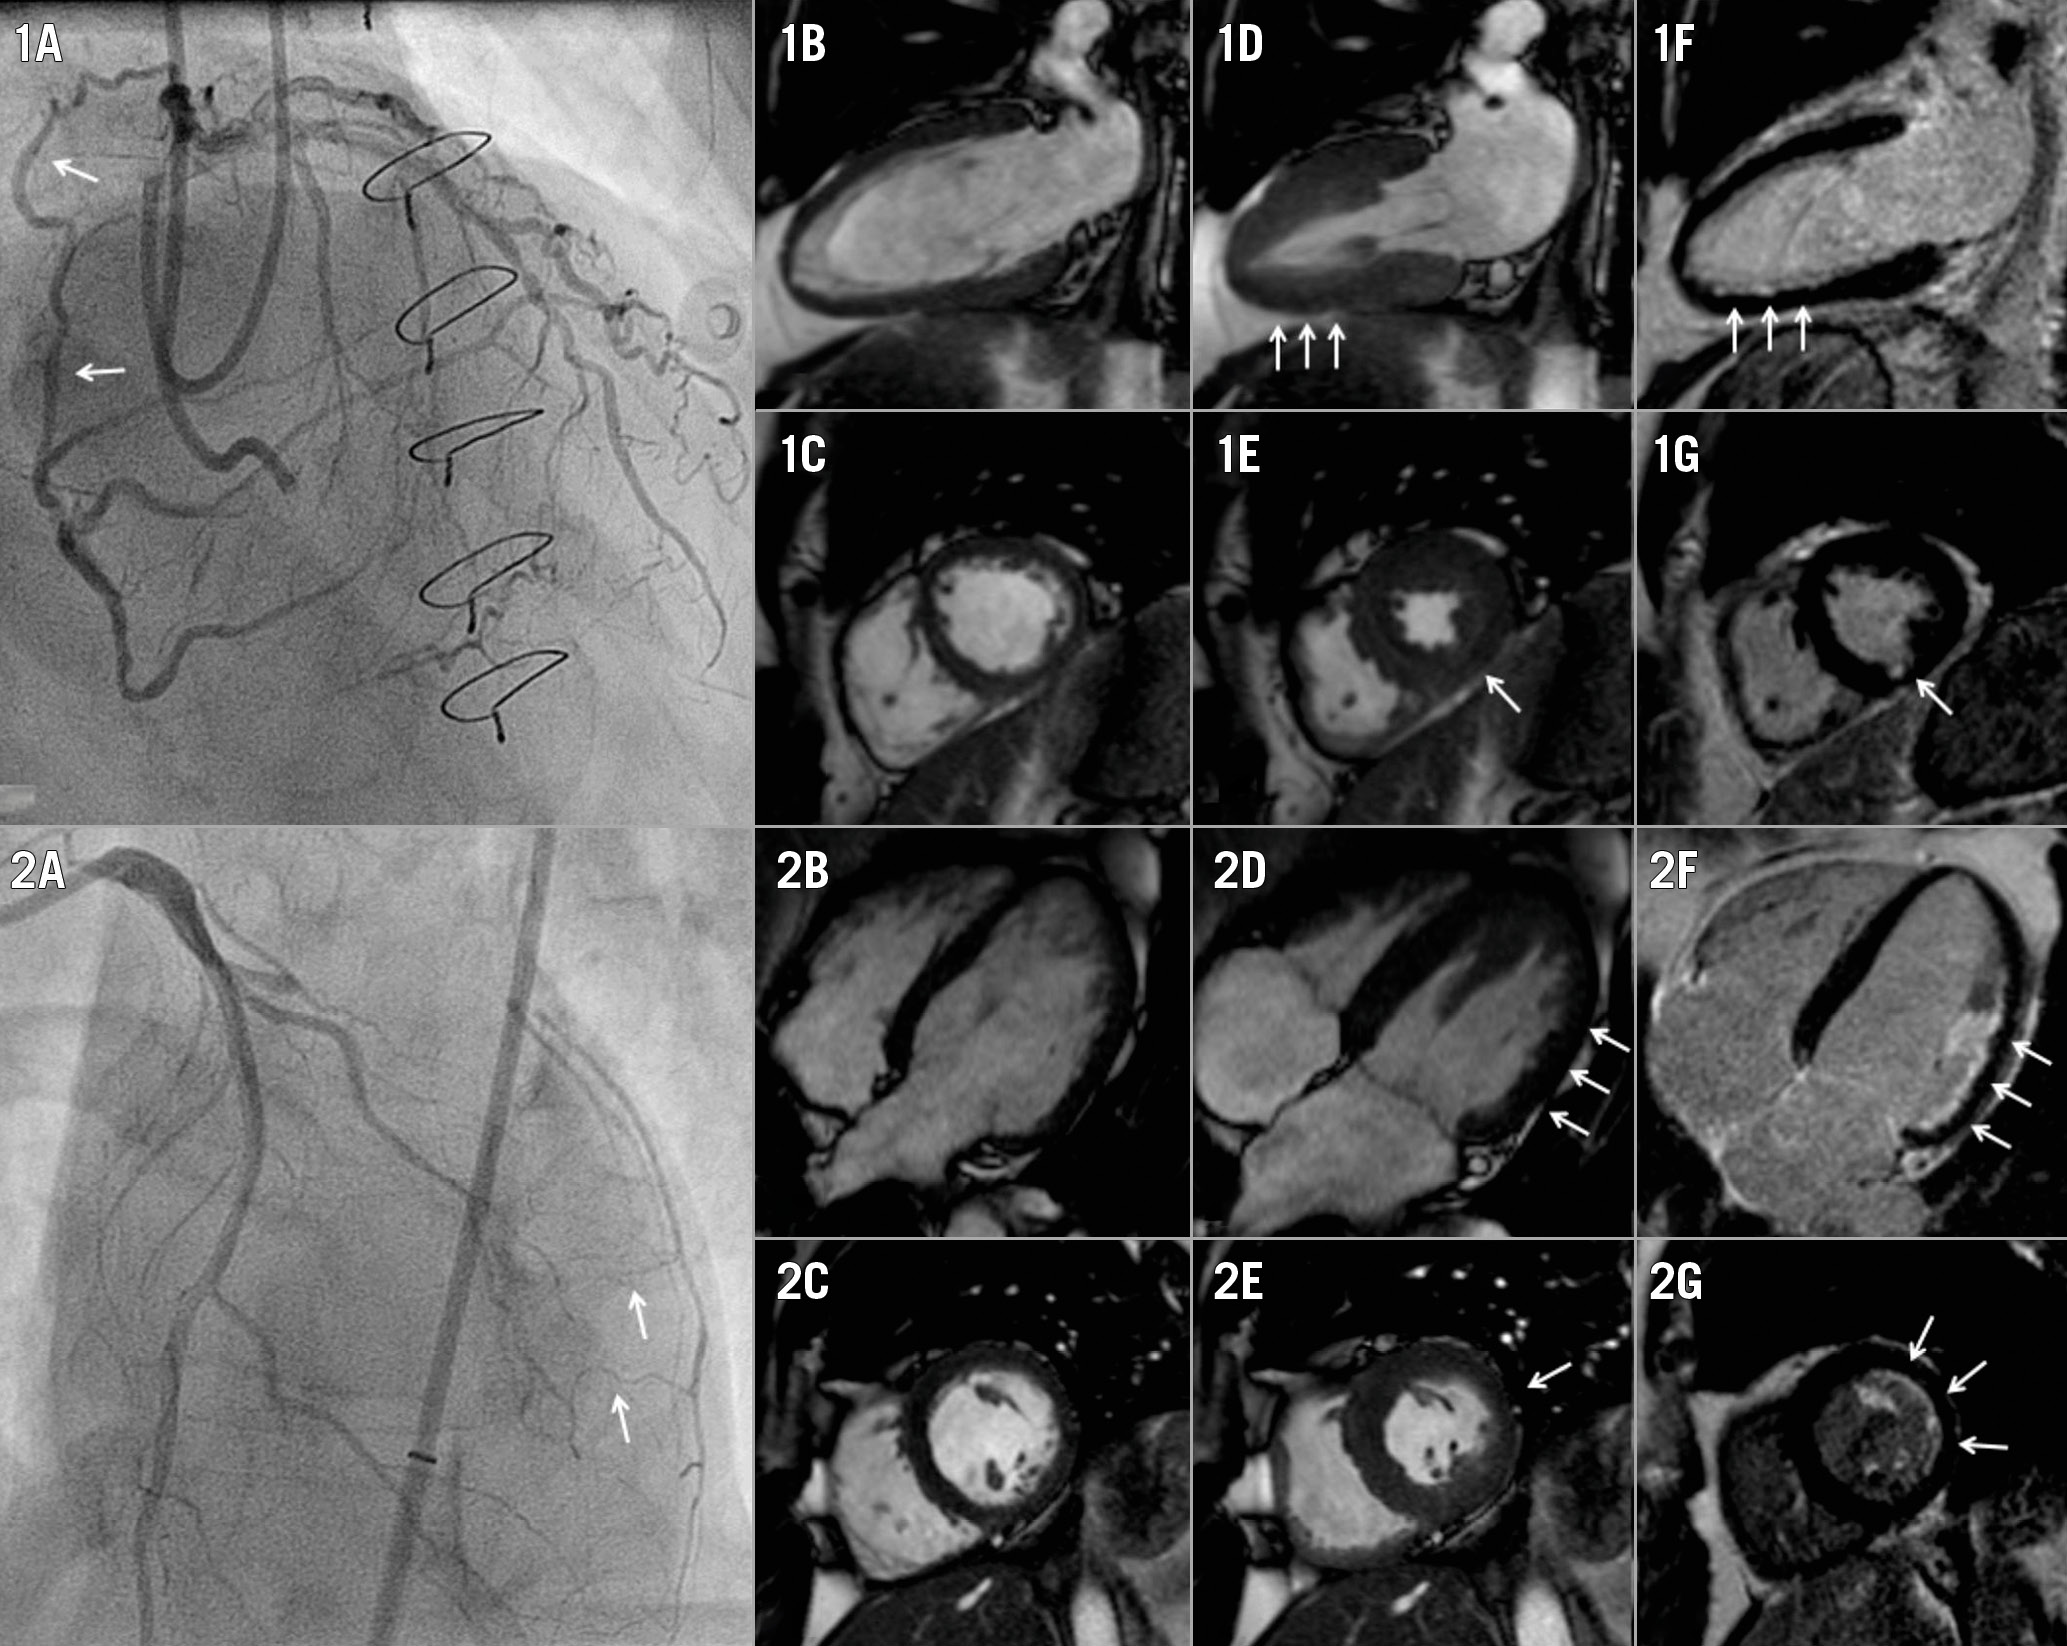

In 147 patients without documented history of MI in the CTO territory, LGE analysis demonstrated myocardial scar in 112 (76%) CTO territories. In total, 183 (84%) patients had myocardial scar in the CTO region, with no difference in the prevalence of scar between patients with WD and PD collaterals (122 [84%] vs 61 [85%] patients, p=1.00). Median percentage scar tissue in the CTO territory, however, was lower in patients with WD collaterals (p=0.048) (Figure 1A). A normal LV function (LVEF >55%), mild dysfunction (LVEF >40-55%), moderate dysfunction (LVEF >30-40%) and severe dysfunction (LVEF ≤30) was observed in 62 (29%), 104 (48%), 29 (13%), and 21 (10%) patients, respectively. Mean LVEF was higher and LV end-diastolic and end-systolic volumes were smaller in patients with WD collaterals compared to patients with PD collaterals (p=0.02, p=0.047 and p=0.03, respectively) (Table 2). Mean SWT in the CTO territory was higher in patients with WD collaterals (p<0.01) (Figure 1B). Patients with multivessel disease had more scar tissue, larger LV volumes and worse LV function (Supplementary Table 3) compared to patients with single-vessel disease. Case examples of patients with WD and PD collaterals are shown in Figure 2. The amount of scar tissue in the LV and CTO territory was inversely correlated with LVEF and mean SWT in the CTO territory (Figure 3A, Figure 3B).

Figure 2. Case examples including patients with WD and PD collaterals. 1A) A WD collateral (arrow) supplies the vascular territory of a CTO in the right coronary artery. Two-chamber and short-axis views at end-diastolic (1B, 1C) and end-systolic (1D, 1E, arrows) phases show mild hypokinesia of the inferior wall, in the presence of limited subendocardial scar (arrows) detected with LGE (1F, 1G). 2A) PD collaterals supply the vascular territory of a CTO in the left circumflex artery. Four-chamber and short-axis views during end-diastolic (2B, 2C) and end-systolic (2D, 2E) phases display moderate hypokinesia (arrows) of the lateral wall, while LGE (2F, 2G) demonstrates a considerable (but still limited) amount of subendocardial scar (arrows). CTO: chronic coronary total occlusion; LGE: late gadolinium enhancement; PD: poorly developed; WD; well-developed